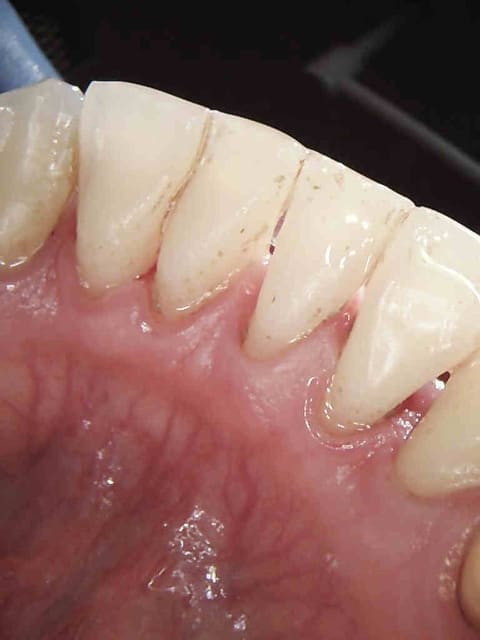

Et le P'ti détartrage qui va bien.

Ça mange pas d'pain et ca fait tjs plaisir

Ci dessous 7 radios, 1 det, une extrac : 118 euros 20 mn. Tu as quelque chose à redire ?